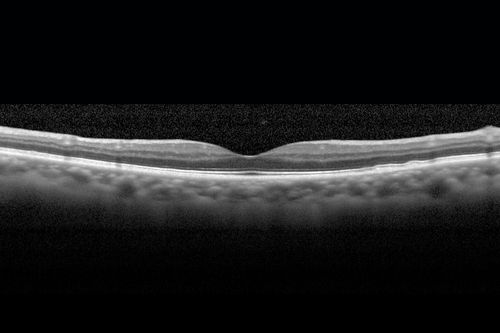

Cystoid macular edema 4 months following cataract surgery with serous retinal detachment

68 year old with 2 months of vision loss OS 20/100. ECCE was 4 months ago.

CME 4 months following cataract surgery with serous retinal detachment